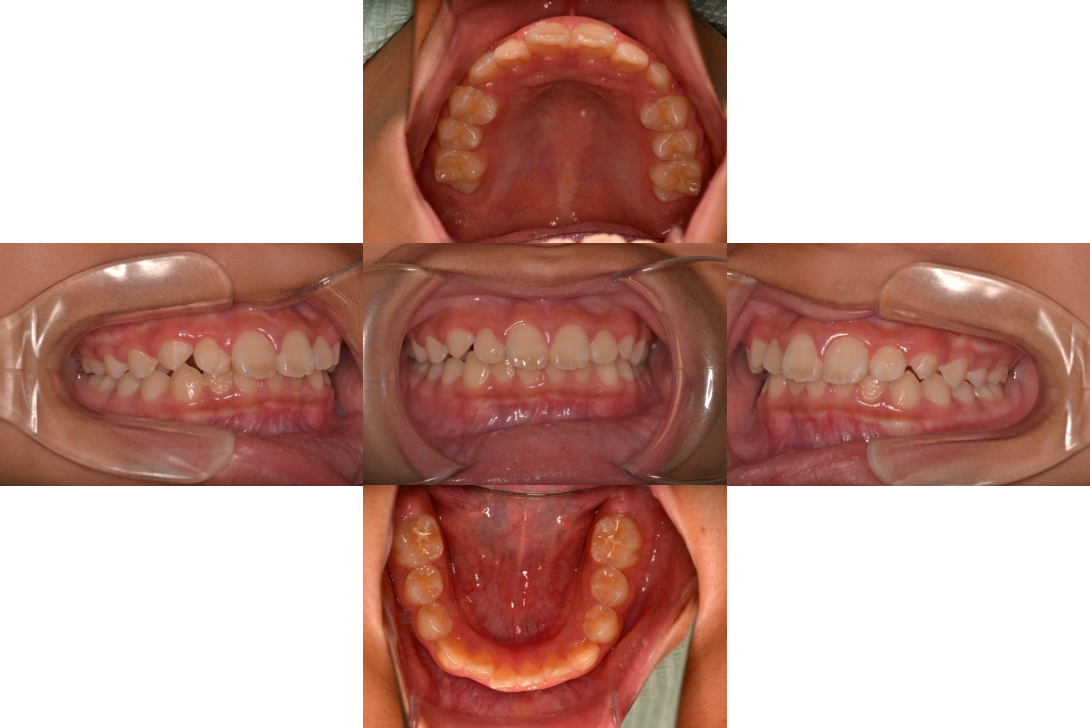

過蓋咬合を抜歯とDBSで改善した症例

※DBSとはダイレクトボンディングシステムと呼ばれており、ブラケットにワイヤーを通して歯を動かしていく矯正治療です。

患者情報

16歳女性

主訴

前歯がでてる

行った治療内容

上顎両側4番抜歯、DBS

治療のリスク

歯根吸収、前歯部歯肉退縮

治療期間

動的治療期間4年0か月

※ クリックして拡大することができます。